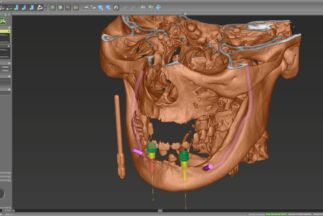

コンピュータによる

外科用ガイド治療計画 -